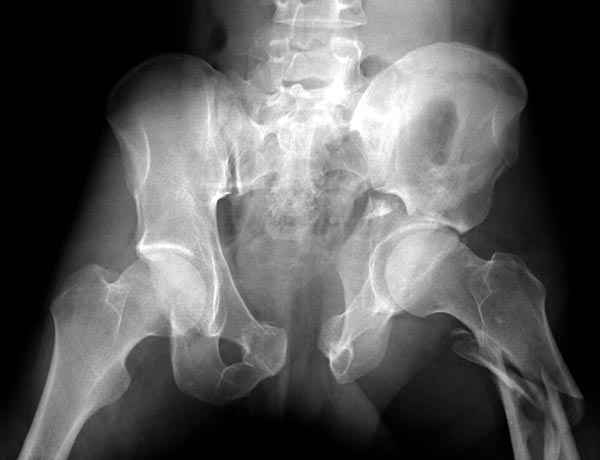

Все выступающие коллеги высказались насчет необходимости стандартных снимков по Judet, потому что для определения тактики лечения переломов вертлужной впадины 3Д снимки малоинформативны.

Летурнель разработал классификсацию на основании прямого, запирательного и подвздошного рентген снимков, котоые, кроме описания характера переломов, также подсказывают адекватный доступ для репозиции перелома.

Из того минимума, что представлено, мне кажется, мы имеем дело с двухколонным переломом вертлужной впадины. Обычно медиальный (центральный) "вывих" головки встречаются в сложных двухколонных переломах со смещением.

Здесь несколько вариантов двухколонных свежих переломов, которые были оперированы из одного-заднего, а также из двух: переднего и заднего доступов.